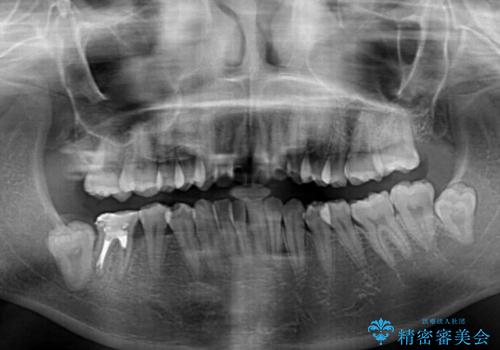

左右ともに奥歯の咬み合わせに問題があり、上顎臼歯が前方位にある状態で、結果として上顎前歯全体が前方位かつ叢生になっていました。

補助装置を用いて上顎歯列全体を後方に移動させ、下顎は左右で抜歯する小臼歯を変えることで、左右の咬み合わせをより理想的な位置となるように計画しました。

埋伏している右下第二大臼歯は、牽引して咬合に参加させることで計画しましたが、癒着などにより移動困難な場合には、抜歯の上インプラント補綴治療を行うこととしました。